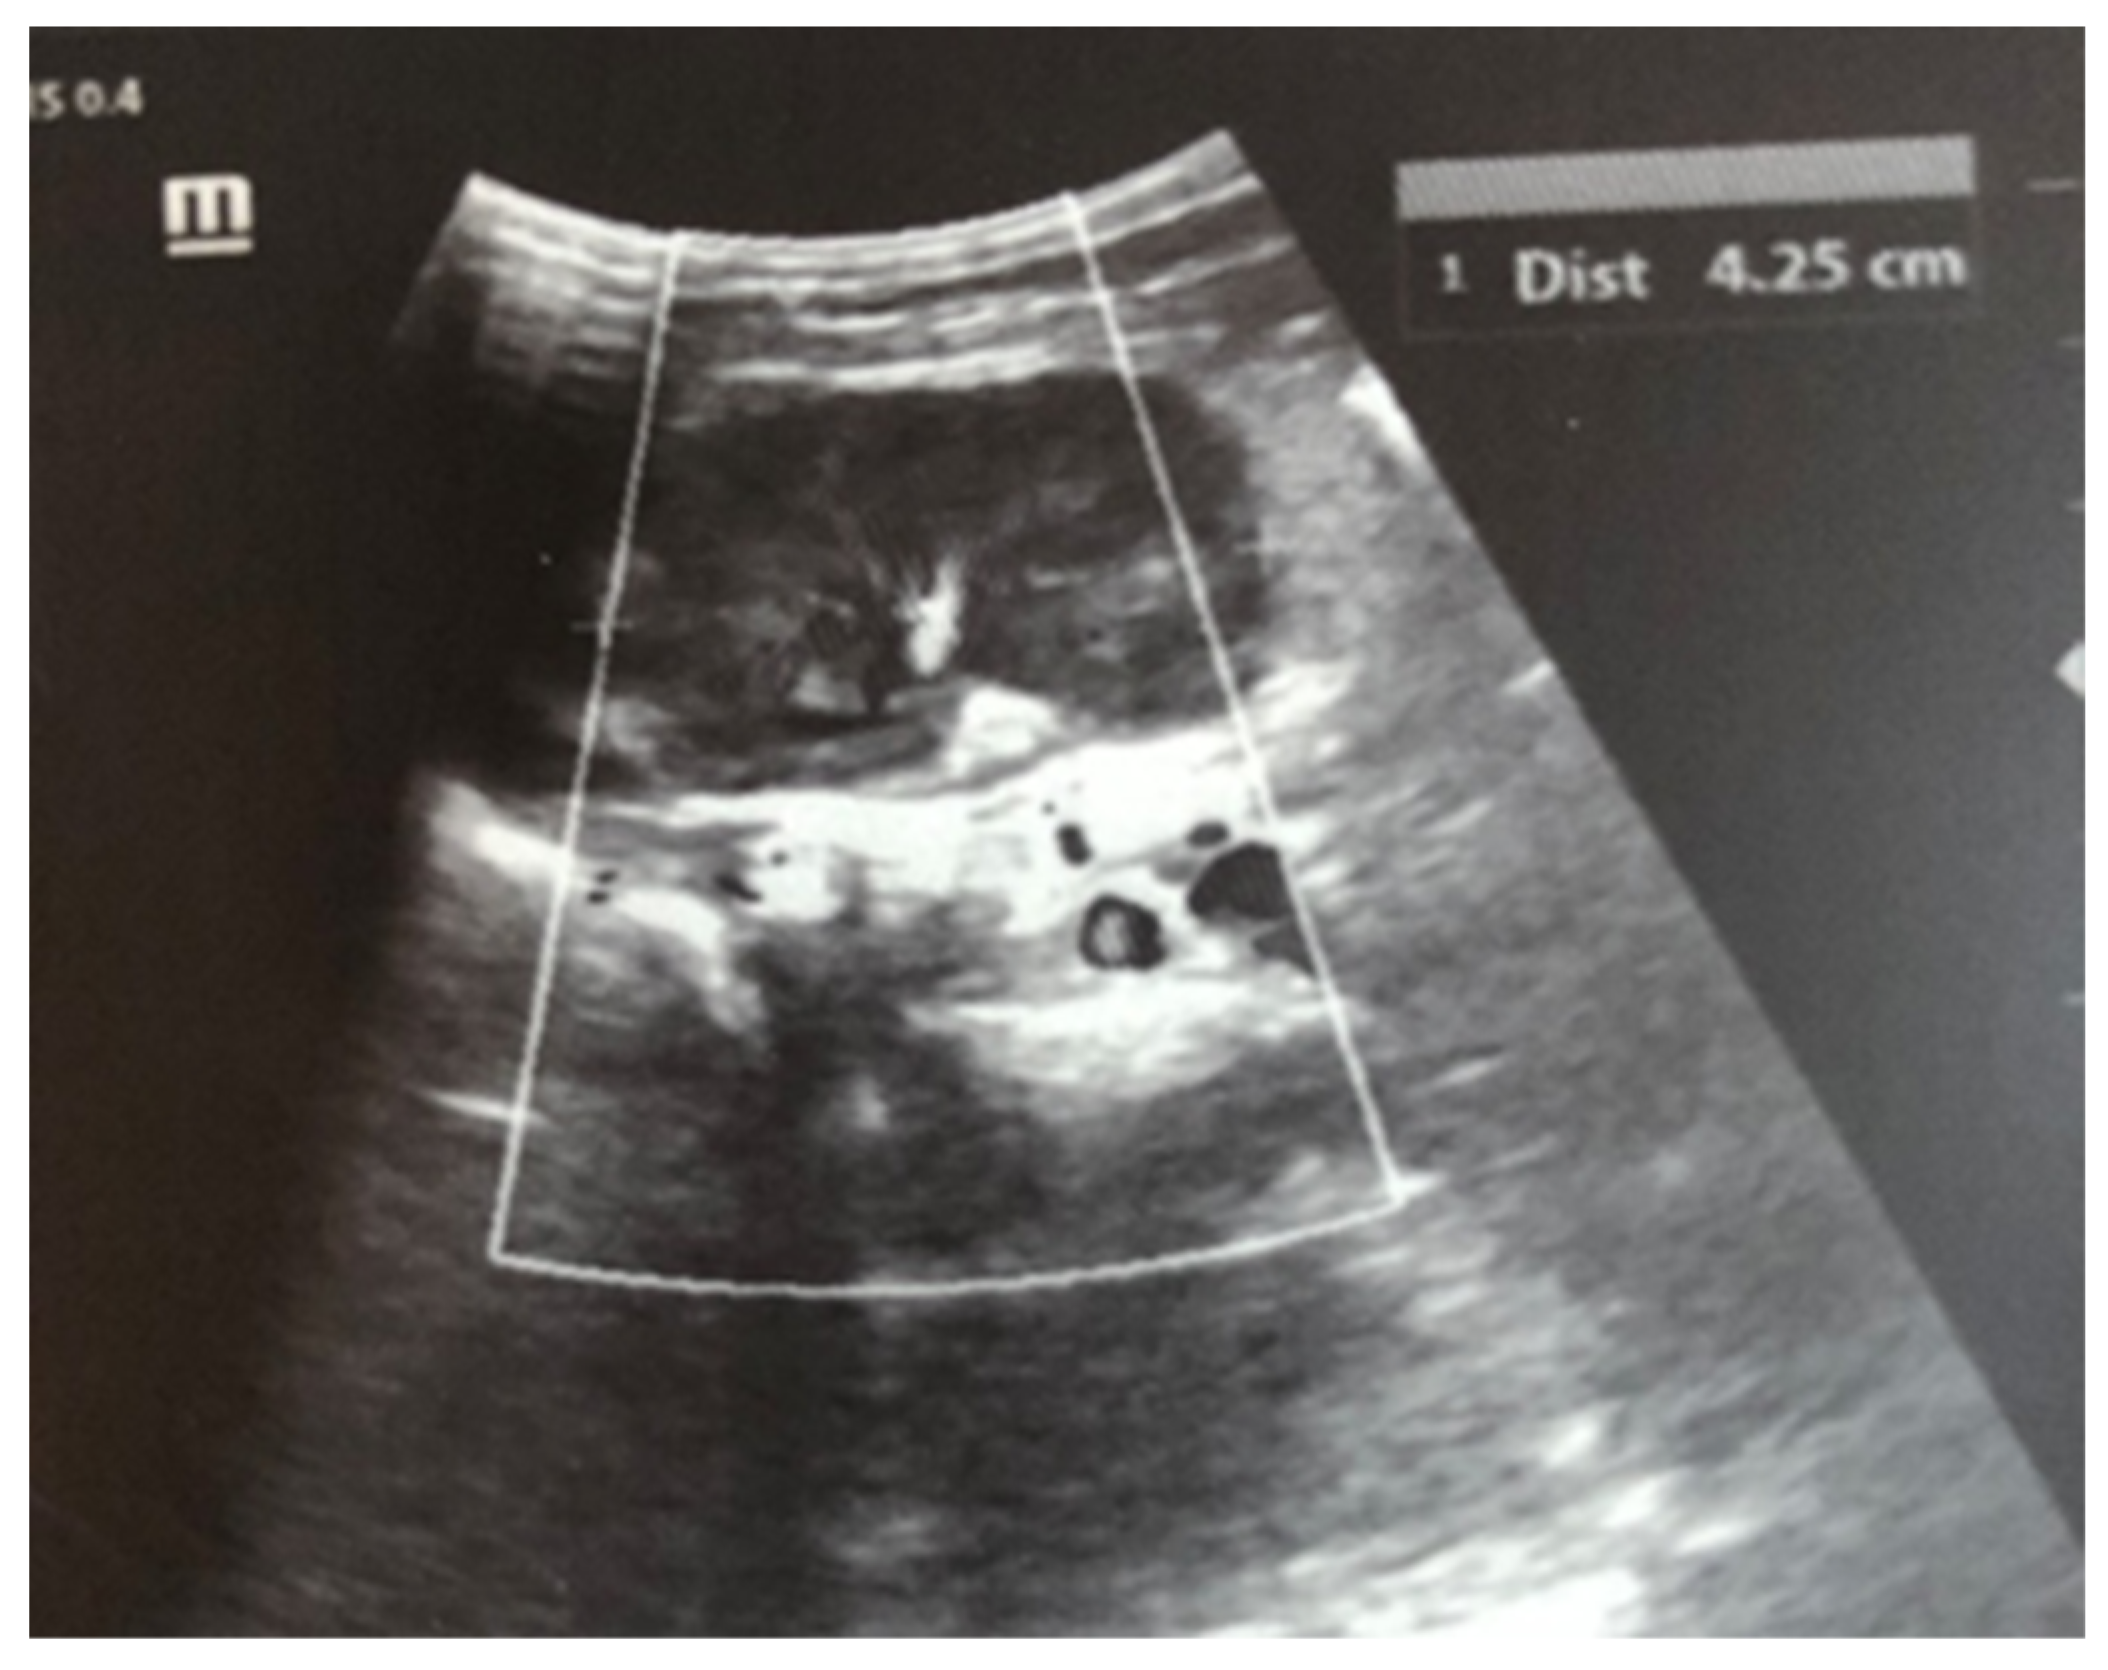

After admission to the NICU, the neonate was found febrile, with symptoms of multiple organ failure: respiratory system failure requiring treatment with Curosurf and mechanical ventilation; renal failure with symptoms of oliguria, macroscopic hematuria, and an increase in nitrogen waste products; the manifestation of neurological symptoms—muscular hypertonia and hyperreflexia, increased convulsive readiness with frequent spontaneous and provoked clonuses of the limbs. The blood tests revealed inflammatory activity—increased CRP and evidence of early nonconjugated hyperbilirubinemia. An abdominal ultrasound examination, performed 2 h after birth, found an enlarged right kidney with a longitudinal size of 6.1 cm, swollen parenchyma with a thickness of 1.8 cm, and increased echogenicity with the presence of interlobar hyperechogenic spikes—an image characteristic of the early phase of renal vein thrombosis. The left kidney—with a longitudinal size of 4.1 cm—preserved the topic, size, and echogenicity of the parenchyma, without drainage disorders, see Figure 1 and Figure 2.

Figure 2. Left kidney image taken in the 2nd hour after birth—the topic, size, and echogenicity of the parenchyma are preserved, without drainage disorders.